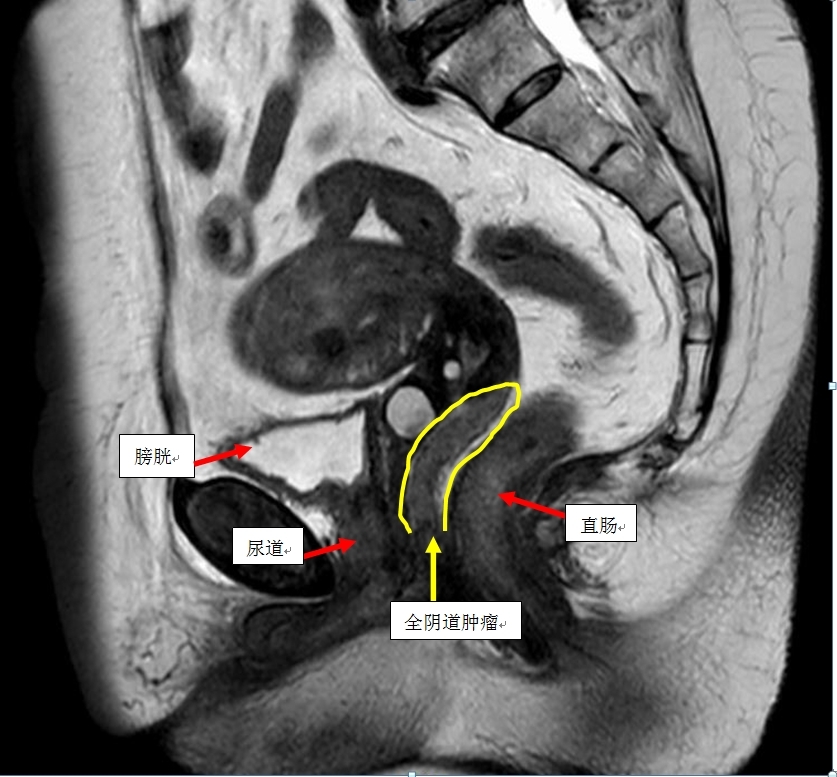

患者黄女士,63岁,因绝经后不规则阴道出血3个月入院,经妇科检查、影像学评估及阴道镜活后,确诊为原发性阴道鳞癌Ib期(肿瘤位于阴道后壁,大小约125px,累及阴道上2/3,浸润深度达直肠壁)。由于肿瘤位置特殊,累及范围广泛,放射治疗难以达到根治效果,并且容易出现放射性肠炎、放射性膀胱炎、肠穿孔、膀胱穿孔等严重并发症易,给患者预后和生命构成严重威胁。

该手术的技术难点主要体现在三个方面:首先,手术解剖结构复杂,毗邻膀胱、尿道及直肠,操作空间狭小,对术者的精准度和技术要求极高,稍有不慎即可能损伤周围重要器官,造成严重并发症。其次,淋巴结清扫范围广,需彻底清除盆腔区域的各组淋巴结,以阻断可能的癌细胞转移途径。最后,全阴道的切除涉及会阴体部的精细重建,对术后患者的功能恢复和生活质量是一大考验。

手术当日,在麻醉科、手术室配合与支持下,由李荻玲主任医师主刀,李伟、梁胜砚两位助手的默契配合,团队凭借丰富的经验和精湛的技艺,细致操作,逐层分离,完整切除子宫、双侧附件、受侵犯的阴道全域以及盆腔淋巴结组织,同时成功保留了尿道和直肠的完整性,成功重建会阴部,术中出血量控制良好,手术历时5小时,最终顺利完成。